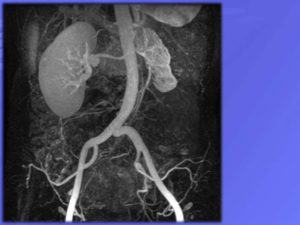

Почки — главный орган мочевыделительной системы, образующий мочу

Почки выполняют несколько жизненно важных функций, но одна здоровая почка может работать так же хорошо, как две

Почка содержит огромное количество нефронов, представляющих собой переплетение сосудистых клубочков и канальцев. Капилляры почечных клубочков непрерывно работают. В результате чего из крови удаляются отработанные продукты жизнедеятельности организма.

Однако в здоровой почке функционирует только часть, примерно 60 процентов нефронов, остальные же до поры до времени находятся как бы в состоянии покоя. Это резерв, который вступает в работу в момент крайней необходимости. Такой момент и наступает, когда одна почка удалена.

Уже через день после операции в работу включается 95 процентов нефронов. И если спустя несколько часов (а иногда и дней) после удаления почки наблюдается замедленное выделение мочи, то уже на 4—8-й день наступает гиперфункция (повышение работоспособности) оставшейся почки, и она начинает полностью справляться с повышенной нагрузкой.